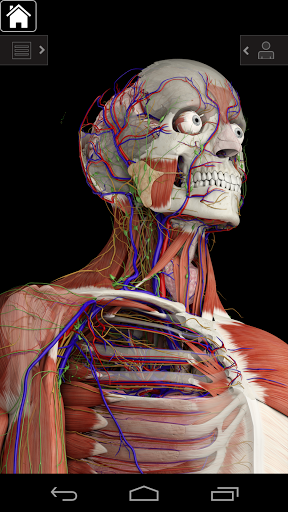

Essential Anatomy 3 representa lo último en tecnología 3D innovadora y diseño innovador. Un motor de gráficos 3D de vanguardia, creado a medida por 3D4Medical desde cero, alimenta un modelo anatómico altamente detallado y ofrece gráficos de calidad excepcional que ningún otro competidor puede lograr.

La aplicación representa un enfoque único para el aprendizaje de la anatomía general. Los gráficos no tienen paralelo y hacen que el aprendizaje, a través del uso de contenido informativo y características innovadoras, sea una experiencia rica e interesante.

NUEVA TECNOLOGÍA 3D

Essential Anatomy 3 es receptivo, visualmente impactante y sin esfuerzo. La aplicación es totalmente en 3D, lo que significa que puedes ver cualquier estructura anatómica de forma aislada y desde cualquier ángulo.